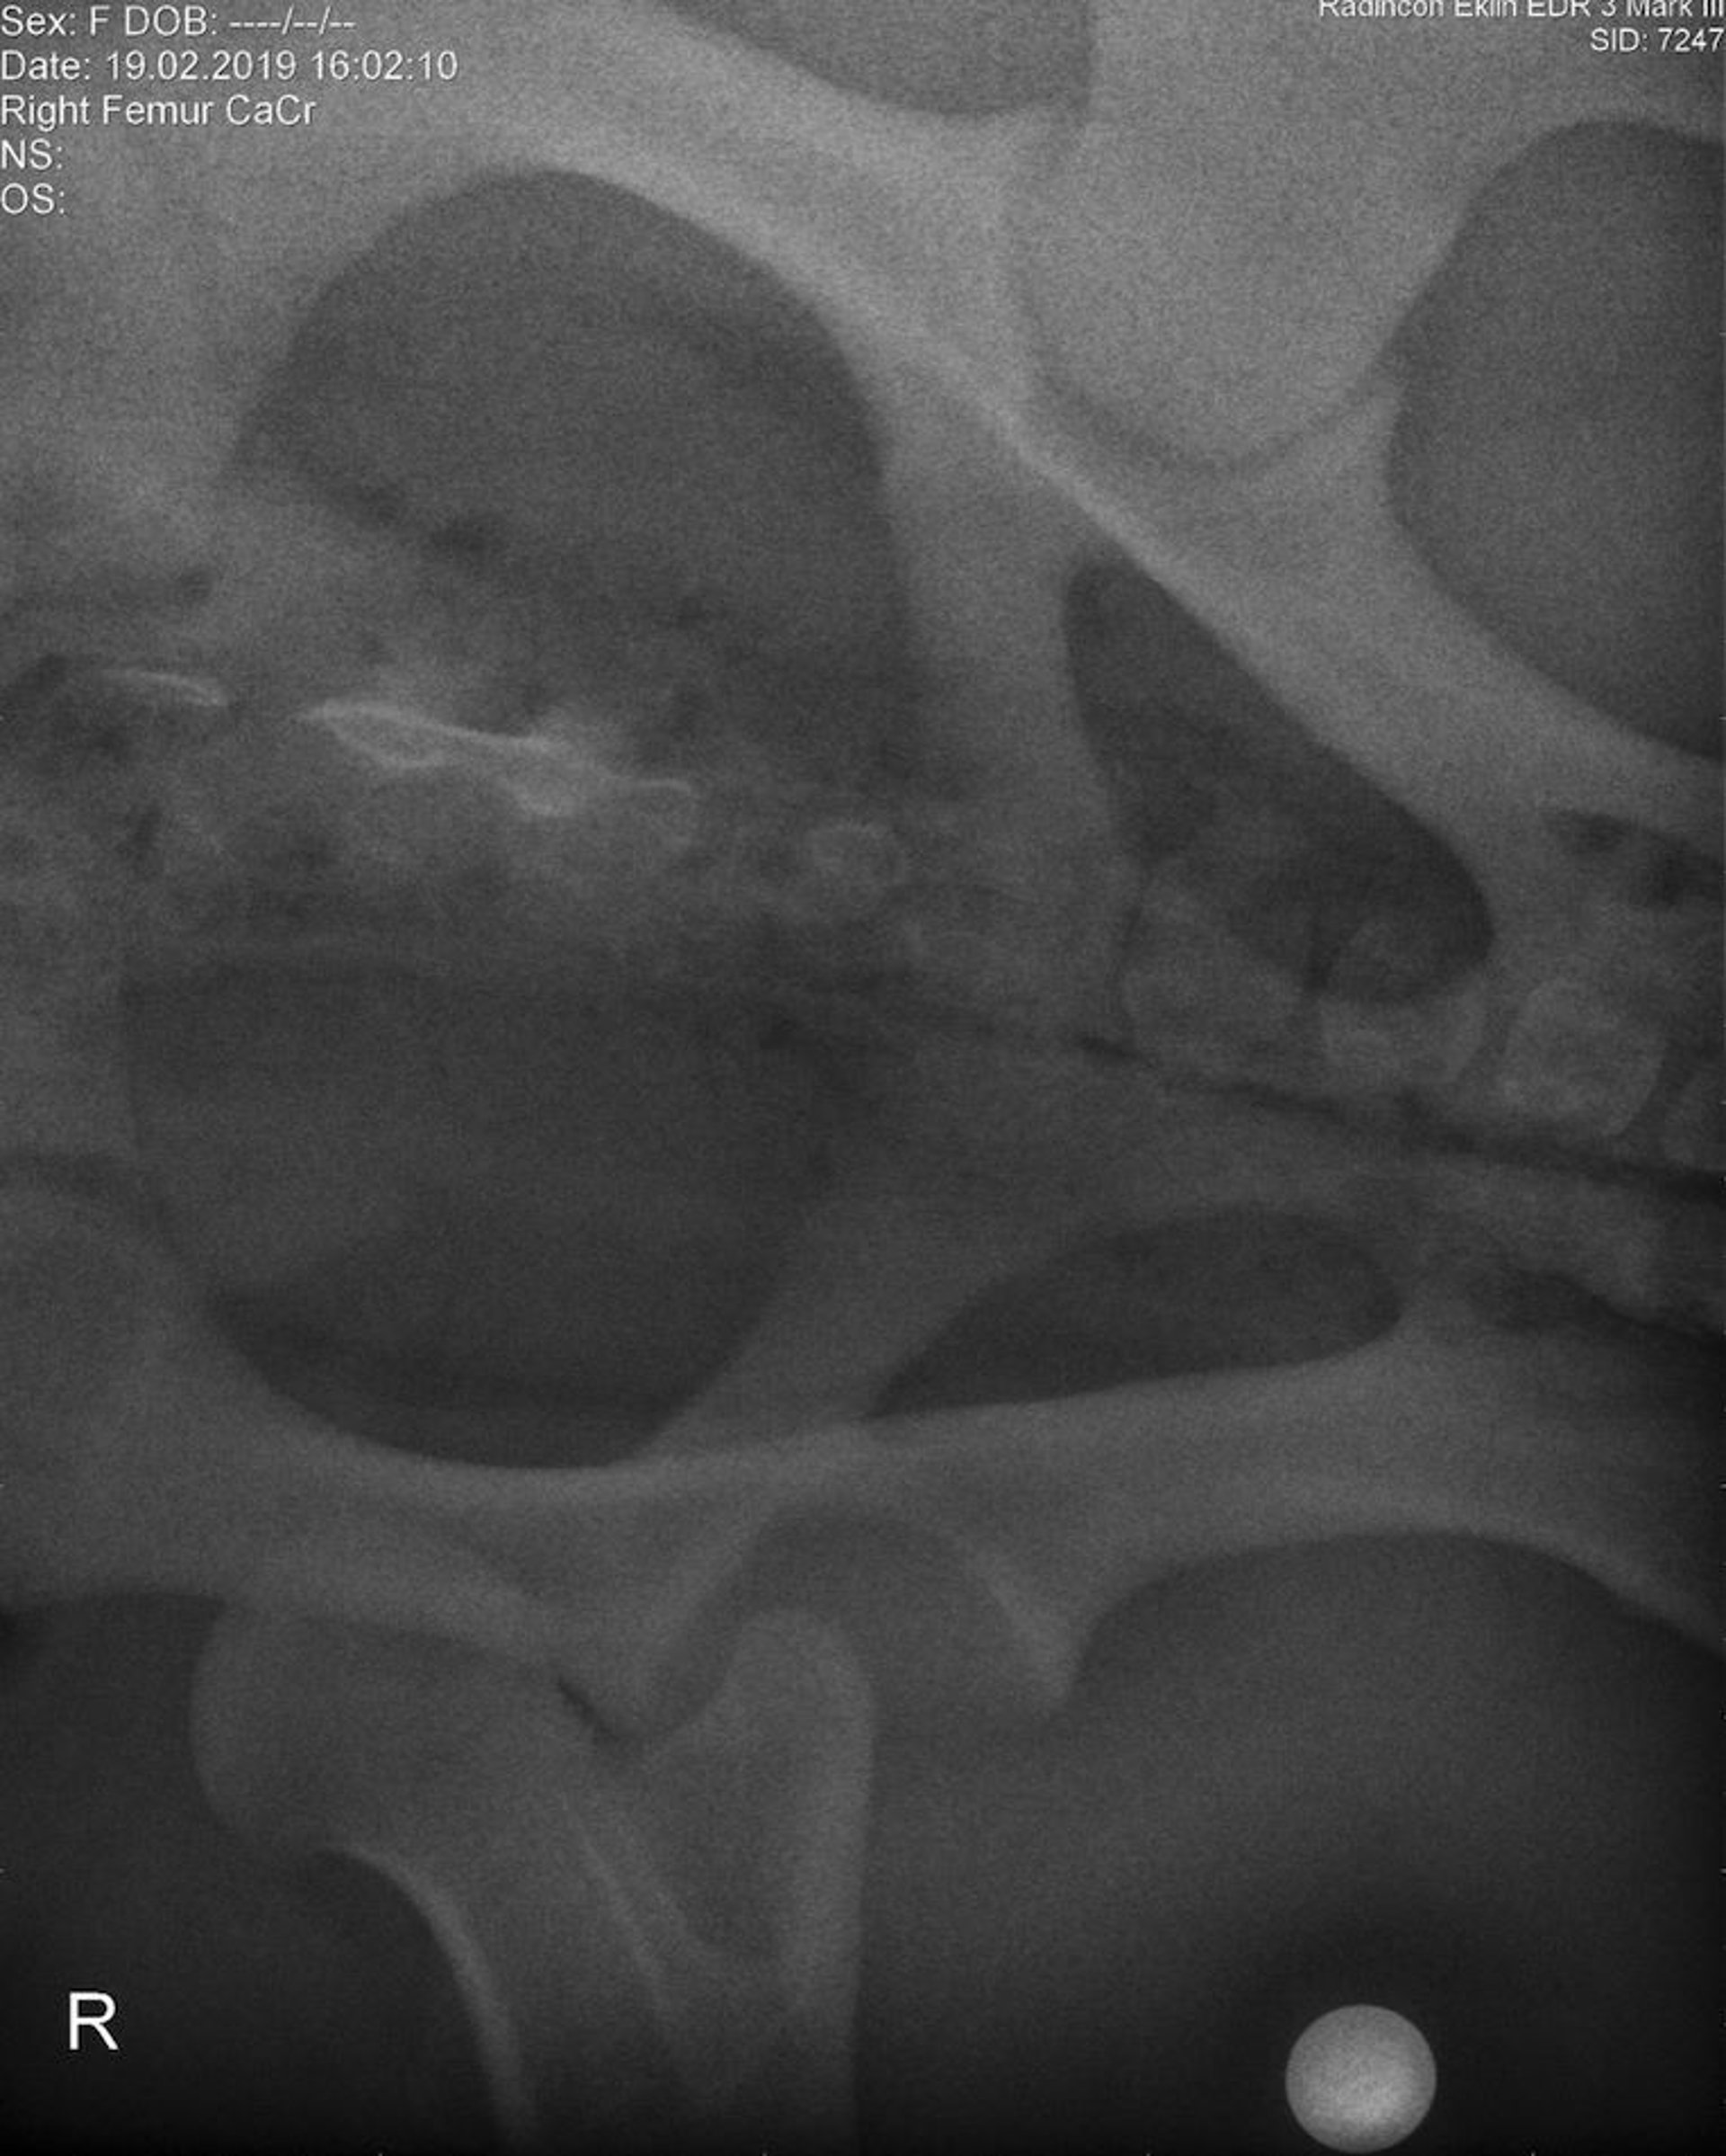

Coxofemoral joint luxation, preoperative ventrodorsal radiograph, pony

Ventrodorsal radiographic image of a pony, obtained with the patient under general anesthesia before surgery, showing luxation of the right coxofemoral joint.

Courtesy of Dr. Louise Cosgrove.